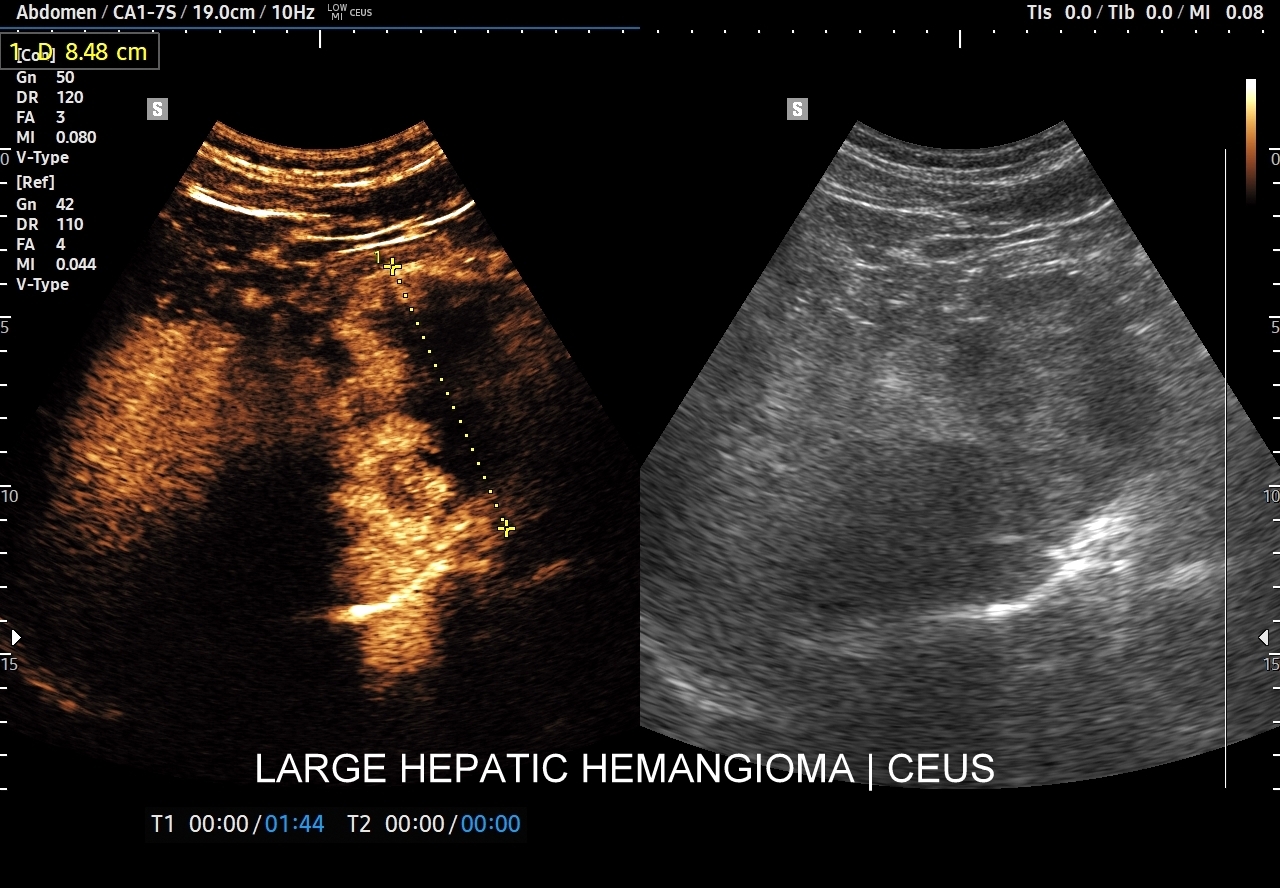

Naczyniaki duże, tj. powyżej 2-3 cm, mogą mieć strukturę niejednorodną echogenicznie, w tym obszary hypoechogenne. Spotyka się także naczyniaki o charakterystyce normo- lub hypechogenicznej, w szczególności w wątrobie stłuszczonej. Z powyższych względów należy mieć na uwadze i zapamiętać, że badanie USG w podstawowym trybie B nie jest wystarczające do postawienia rozpoznania naczyniaka wątroby. W ramach obrazowej diagnostyki różnicowej najbardziej pomocnym jest badanie USG z kontrastem (CEUS), w którym to naczyniak wątroby posiada charakterystyczny wzorzec wypełnienia.

Najbardziej charakterystyczną cechą naczyniaka wątroby w badaniu CEUS jest jego wypełnianie w postaci guzkowej (ang. peripheral nodular enhancement) od obwodu ku centrum zmiany (ang. centripetal). Szybkość wypełniania bywa różnorodna, może być powolna lub szybka. W przypadku szybkiego wypełniania (tzw. flash-filling), w celu wykazania charakterystycznego centrypetalnego wypełniania niezbędna może być postprocessing’owa analiza poklatkowa zapisanego nagrania badania. W fazie późnej naczyniak wątroby pozostaje izowzmocniony lub hyperwzmocniony w stosunku do natywnego miąższu wątroby.

W przypadku dużych naczyniaków obszary, które uległy wykrzepianiu pozostają awaskularne przez wszystkie fazy badania CEUS, tj. nie wypełniają się kontrastem (nonenhancing). W przeciwieństwie do powyższego konstelacja, w której to w fazie wczesnej pojawia się wzmocnienie, a następnie w fazie wrotnej lub późnej ulega wypłukaniu (hypoenhancement) świadczy o cechach złośliwych diagnozowanej zmiany ogniskowej w wątrobie i wyklucza rozpoznanie naczyniaka.